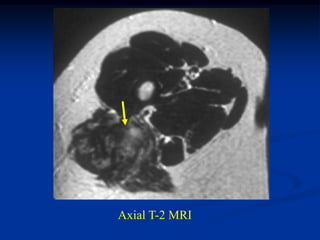

Case #263           Coronal proton density MRI

tumor

72 year female with MFH deltoid muscle

Another proton density coronal cut